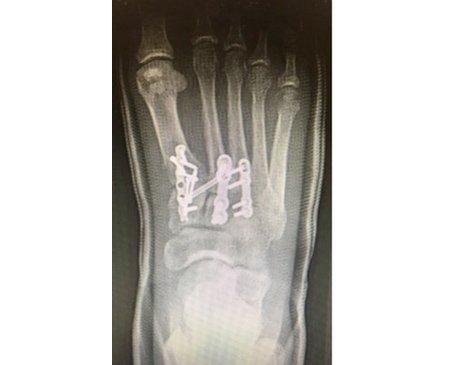

Before and after x rays of a Pilon fracture. A Pilon fracture is a type of ankle fracture that involves the ankle joint. It is critical to appropriately align the ankle joint surfaces when fixing these fractures with surgery. In some instances, intraoperative arthroscopy can aid in direct visualization of the joint without opening the joint to help better align the joint surfaces.